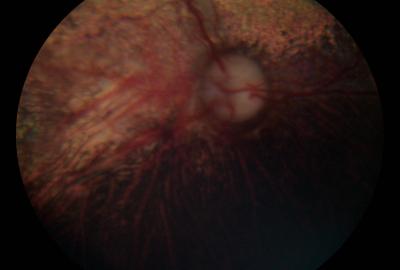

CEA | Veterinární klinika Medipet Zlín

Sítnice - normální nález | Veterinární klinika Medipet Zlín